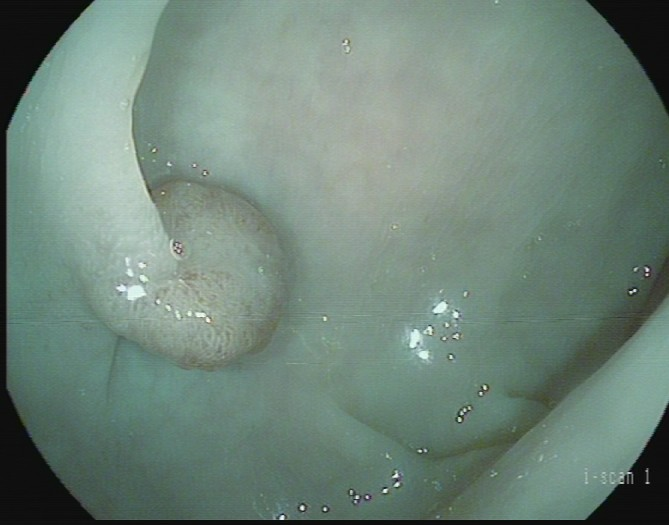

(4)黄先生(32岁,升结肠息肉,图4)

图4

病理诊断:潴留性息肉(或称幼年性息肉)。

解读:这类息肉常见于儿童和青少年,但成人也可发生。是黏膜腺体扩张、分泌物潴留形成的错构瘤性病变,本质上是良性,通常不具有癌变潜能。距离癌:基本安全,良性息肉。